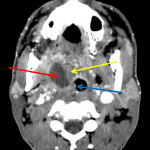

- Low density collection with peripheral enhancement adjacent to the right palatine tonsil which exerts mass effect upon and mildly narrows the adjacent airway

- Peritonsillar abscess

Right peritonsillar abscess measuring x by x with mild mass effect upon and narrowing of the adjacent pharyngeal airway.

Mucosal enhancement of the pharynx represents pharyngitis without retropharyngeal edema.

Reactive cervical adenopathy. No venous thrombosis.